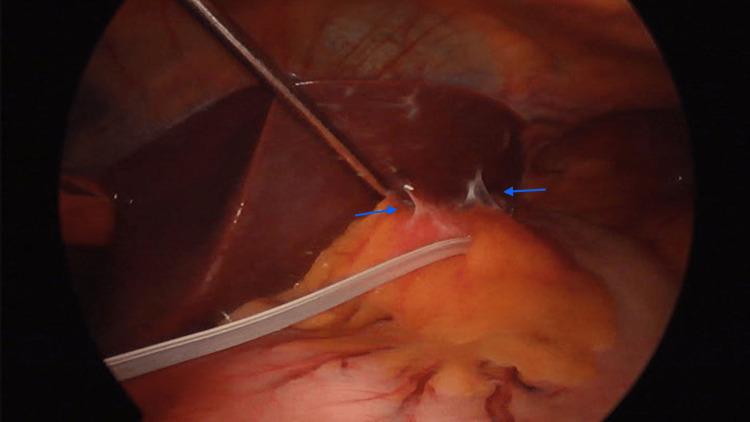

In the context of adjustable gastric band (AGB) placements and the prevalent issue of weight regain with associated complications, revision surgery for gastric bands becomes imperative. Such revisions may encompass band removal or conversion to bariatric procedures, often accompanied by an escalated risk profile, potentially contributing to a 20% morbidity rate. Laparoscopic sleeve gastrectomy (LSG) has gained prominence due to its technical simplicity, effectiveness in weight loss, and lower complication rates. Specific cases involving LSG post-AGB complications are associated with staple line disruptions and leaks. This case report describes a rare complication in a 59-year-old patient following AGB removal and subsequent laparoscopic sleeve gastrectomy. The complication emerged six hours after the surgery, with approximately 400 cc of bile material reported in the drainage. A laparoscopic reintervention was conducted, revealing bile leakage from the second Couinaud hepatic segment. Successful management of the leakage was achieved through simple hepatic suturing using non-absorbable monofilament. Within 24 hours, no further leakage occurred, and the patient was discharged without additional complications. Our case also demonstrates how complex it can be to switch between different medical procedures, and it emphasizes the need for careful planning and precise surgery in the evolving world of bariatric medicine. It is worth noting that there is a dearth of literature addressing this specific complication. Consequently, this study has the potential to provide valuable insights for surgeons who may encounter a similar scenario in their clinical practice.

在可调节胃束带(AGB)置入以及体重反弹及相关并发症这一普遍问题的背景下,胃束带修复手术变得势在必行。此类修复手术可能包括移除束带或转换为减肥手术,通常伴随着风险的增加,可能导致20%的发病率。腹腔镜袖状胃切除术(LSG)因其技术简单、减肥效果显著以及并发症发生率较低而备受关注。涉及AGB术后并发症的LSG具体病例与吻合口破裂和渗漏有关。本病例报告描述了一名59岁患者在AGB移除及随后的腹腔镜袖状胃切除术后出现的罕见并发症。该并发症在手术后6小时出现,引流液中报告有约400毫升胆汁样物质。进行了腹腔镜再次干预,发现胆汁从第二肝段库氏段渗漏。通过使用不可吸收单丝进行简单的肝脏缝合成功处理了渗漏。24小时内未再发生渗漏,患者出院且无其他并发症。我们的病例还表明,在不同医疗手术之间转换可能有多复杂,并强调在不断发展的减肥医学领域进行仔细规划和精确手术的必要性。值得注意的是,针对这一特定并发症的文献匮乏。因此,本研究有可能为临床实践中可能遇到类似情况的外科医生提供有价值的见解。